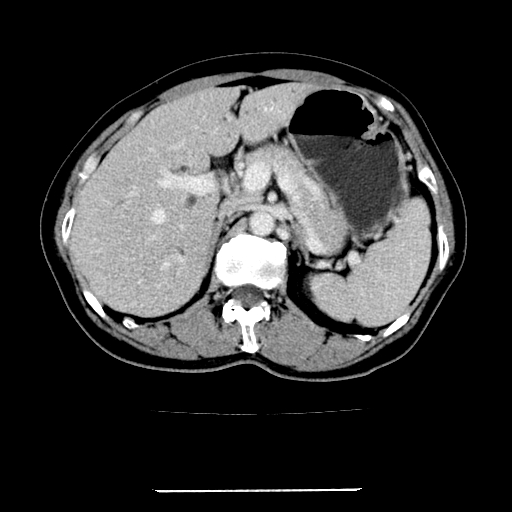

标题: CT22301:女,67岁,上腹部疼痛一周伴皮肤黄染,无发热。 [打印本页]

女,67岁,上腹部疼痛一周伴皮肤黄染,无发热。

左叶肝内胆管结石,并远端肝内胆管扩张。

支持肝内胆管结石并肝内胆管扩张。

肝内外胆管结石并肝内胆管扩张。

肝内外胆管扩张,左叶胆管内结石

建议薄层观察,除外肝门部胆管细胞癌

1、肝门高密度影下层面和胰头层面可见轻度胆管扩张,而静脉和延迟期均未见扫描完胰头,不能完全排除胰头占位。2、肝门部高密度影,考虑钙化或结石。